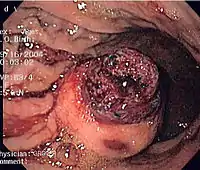

CT scanning is often undertaken (see the radiology section).

The definitive diagnosis is made with a biopsy, which can be obtained endoscopically, percutaneously with CT or ultrasound guidance or at the time of surgery. A biopsy sample will be investigated under the microscope by a pathologist physician. The pathologist examines the histopathology to identify the characteristics of GISTs (spindle cells in 70-80%, epitheloid aspect in 20-30%). Smaller tumors can usually be confined to the muscularis propria layer of the intestinal wall. Large ones grow, mainly outward, from the bowel wall until the point where they outstrip their blood supply and necrose (die) on the inside, forming a cavity that may eventually come to communicate with the bowel lumen.

When GIST is suspected—as opposed to other causes for similar tumors—the pathologist can use immunohistochemistry (specific antibodies that stain the molecule CD117 [also known as c-kit] —see below). 95% of all GISTs are CD117-positive (other possible markers include CD34, DOG-1, desmin, and vimentin). Other cells that show CD117 positivity are mast cells.

If the CD117 stain is negative and suspicion remains that the tumor is a GIST, the newer antibody DOG-1 (Discovered On GIST-1) can be used. Also sequencing of Kit and PDGFRA can be used to prove the diagnosis.